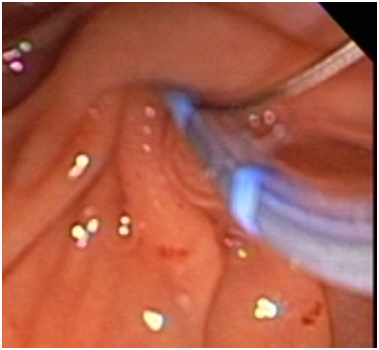

68-year-old female with presence of secondary hypothyroidism 8 years of evolution in treatment with levotiroxin, systemic hypertension 2 year of evolution treated with losartan, thyroidectomy 8 years ago, c-sections 243 and 38 years ago, the patient denies the use of alcohol or tobacco. Initiates with sudden transitive pain in epigastrium, vomiting several times, undergoing imaging and laboratory tests diagnosing pancreatitis its determined that the patient is in need of a ERCP, which is performed at a private institution, during the procedure the major duodenal papilla is identified anatomically normal but without bile output with multiple cannulation attempts (Figure 1), continuing with procedure applying contrast appreciating two gallstone suggesting images in distal choledocus which measures 9 mm in diameter (Figure 2) with a probable stenotic area in the distal portion, a wide sphincterotomy is performed with posterior passing of extraction balloon doing multiple sweeps obtaining two 7 mm gallstones due to said area of stenosisa 10 fix 10 cm stent is placed towards the right hepatic duct. After the procedure the patient presents moderate to intense pain in right hypochondrium alongside hypotension, administrating crystalloids and vital sing stabilization ordering CT scan where a sub capsular collection is visualized, varying heterogenicity from 600 to 20 HU, highly suggestive of a serohematic component with approximate size of 17 by 13.8 by 6.5 cm, with approximate volume of 820 cc (Figure 3) (Figure 4) with diagnosis of a probable subcapsular hematoma, with later presentation of acute kidney failure requiring temporary renal substitution therapy, once she was hemodynamically stable its moved to our unit to continue treatment, taking laboratory exams determining hyperbilirubinemia, due to conjugated bilirubin and elevated liver enzymes, deciding to do new CT scan where a 20% diminution of hematoma size is appreciated and adding pleural effusion to the findings deciding to give a conservative management, eight days later performing control ultrasound finding hematoma with a tendency to re absorption .

Figure 1 Endoscopic retrograde cholangiopancreatography: Canned oddi sphincter.

Figure 2 Fluoroscopy with introduction of the guide.